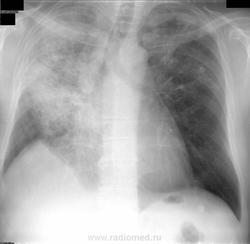

50 лет. Вич - отрицательный. Поступил  вчера. Болен 2 мес. Состояние средней тяжести.  Нарастает одышка. Кашель сухой.  Температура тела 37,5 С  не более. Лейк. 20 тыс. эозинофилы 40%, СОЭ - 70мм/ч. Повторили ан. крови, эозин. опять 38%.  Социально благополучен. О каком заболевании можно думать при таких данных?  Жду. Nikolas

Я бы рекомендовал КТ, для исключения онкологии. Ателектаз в средней доли правого лёгкого, снижения пневматизации по всем полям справа.

Сегодня мне сообщили. У больного установлен окончательно Синдром Черджа- Стросс (СЧС). Краткое сообщение об этой болезни. Относится к группе заболеваний,  "легочные эозинофилии". Изменения на рентгенограммах  и КТ не являются специфическими для СЧС. Инфильтраты в лёгких различной протяженности и плотности, часто мигрирующие, обнаруживаются у 2/3 больных. Реже наблюдаются узелковые центрилобулярные изменения, утолщения стенок бронхов, внутригрудная лимфаденопатия, плевральный и перикардиальный выпот ( последние два признака отмечены на КТ у нашего больного). Ретроспективный пересмотр рентгенограмм позволяет это заметить. С уважением ко всем Вам за Ваше участие в диагностике заболевания. Nikolas.

Б-й  50 лет. Профанамнеза нет. Поступил в терапевтический стационар с жалобами на ощущение заложенности в грудной клетке, затруднённое дыхание, малопродуктивный кашель, одышку в покое,  потливость, выраженную слабость, повышение температуры тела до 37,5 С.

Анамнез заболевания. В течение  2 лет  беспокоит периодически возникающий приступообразный кашель, заложенность носа. Состояние расценивалось как хронический фарингит, аллергический ринит. В мае 2011 г. выставлен диагноз – бронхиальная астма лёгкого течения. У больного была диагностирована аллергия на домашнюю пыль,  клещ домашней пыли и другие.  От лечения ингаляционными глюкокортикостероидами  больной отказался из-за предубеждения о «вреде гормонов  для организма».  В январе 2012   обратился в частную клинику тибетской медицины,  где начал проходить лечение (иглоукалывание, травы) по поводу бронхиальной астмы. После первых сеансов у пациента появились головные боли, слабость. Однако сладкоголосые тибетские Серены ему шептали в уши: «Это так должно быть и скоро ты будешь летать». Но с каждым днем ему становилось все хуже, хуже. Нарастала общая  и мышечная слабость. Больной едва-едва ходил на работу. После последнего сеанса, по дороге на работу,  упал и был доставлен в больницу.

В ходе обследования обращало на себя внимание увеличение уровня лейкоцитов (20*109 /л) и эозинофилов  (40 %),  лимфопения (7%), СОЭ – 70 мм/ч при нормальном уровне гемоглобина,  повышение уровня IgЕ до 461 МЕ/мл. СРБ - резко положительный, гипергаммаглобулинемия. А анализах мочи патологических изменений не обнаружено.  Ан. мокроты: эритроциты 60-80 в п-зр,  эозинофилы 20-30 в п/зр, альвеолярные макрофаги – большое кол. МБТ, грибы не найдены. Спирография - выраженные нарушения вентиляционной способности легких смешанного типа. Бронхоскопия. 2- сторонний поверхностный эндобронхит (1 ст). Микрофлора не выделена.  В анализе кала без особенностей, гельминты и яйца глистов не обнаружены.  Анализы крови на p-ANCA, биопсия легочной не сделаны по объективным причинам.  Следует отметить, что только у 48–66 % пациентов в периферической крови определяются p-ANCA. Данные КТ при поступлении (см. рисунки). Наличие аллергии , аллергического ринита, бронхиальной астмы, гиперэозинофилии, лёгочных инфильтратов,  выпота в плевральной  полости, перикарде, лейкоцитоза, повышения СОЭ, повышения уровня СРБ, выраженной слабости, лихорадки позволили высказать предположение о синдроме Черджа-Стросса. Указанные признаки соответствовали второй фазе болезни.

В результате лечения исчезли признаки бронхиальной обструкции, уменьшилась эозинофилия периферической крови до 6 %, СОЭ снизилась до 22 мм/час. По данным КТ органов грудной клетки (будут представлены позже) отмечена  выраженная положительная динамика в лёгких.  Выпот в плевральной полости и перикарде не определялся. Увеличение лимфатических узлов средостения сохраняется. В удовлетворительном состоянии больной выписан под наблюдение ревматолога. Приведённое наблюдение с оценкой течения заболевания указывает на типичное течение синдрома Черджа–Стросса, несмотря на отсутствие морфологического подтверждения. Специалистов сайта по КТ очень прошу дать характеристику выявленных изменений в ОГК. Пока все. Nikolas.